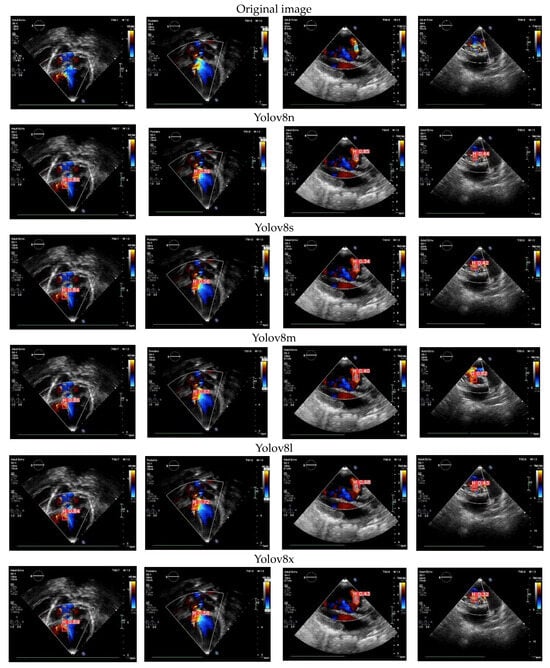

3.8. Color Doppler Echocardiography Case

In this study, we tested the proposed model using color Doppler echocardiography. The predicted outcomes for the cardiac defects are visualized in Figure 11, displaying the results from five Yolov8 architectures. These models are trained to identify specific views required for evaluating CSDs and detect the presence of cardiac defects. In this depiction, the US video utilizes red to represent blood flow toward the transducer and blue to signify blood flow away from the transducer [4]. This capability enables our proposed model of cardiac defect detection to be available not only for the original echocardiography but also with the additional insights provided by color Doppler echocardiography. Among the five proposed architectures, Yolov8l consistently delivers a satisfactory performance and effectively detects holes in the septum. The resulting confidence values exhibit considerable variability, spanning from 0.84 to 0.43. This range of confidence values signifies the model’s adeptness in detecting CSDs through color Doppler echocardiography.

Utilizing DL in color Doppler echocardiography for detecting CSDs offers numerous advantages [3,4]. It streamlines the evaluation of echocardiographic videos, a typically time-intensive process necessitating expert clinical skills. DL can automate this task, saving valuable time and resources. Furthermore, DL models are capable of discerning intricate patterns within echocardiographic images that may elude human experts, enhancing the potential for precise diagnoses [5]. This integration of DL technology holds promise for improving the efficiency and accuracy of CSD detection in clinical settings.

Figure 11. The proposed model of CSD detection in color Doppler echocardiography case.